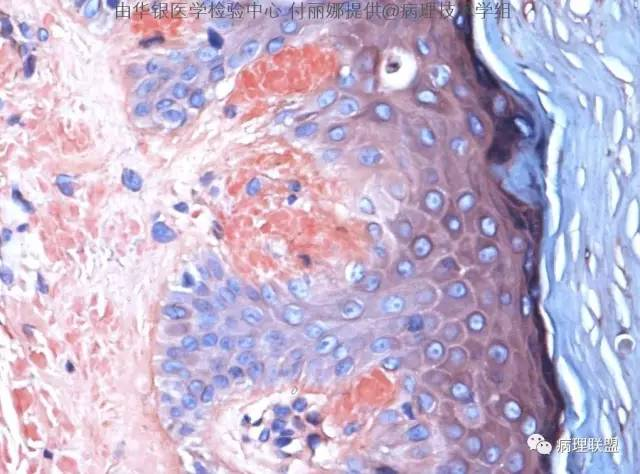

【病理技术】刚果红染色技术及应用

刚果红染色技术及应用